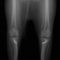

■ 症例24 キャバリア 7か月

左右膝蓋骨内方脱臼(左:グレードⅣ 右:グレードⅢ)

以前から左右後肢の跛行が認められ、整形外科学的検査・レントゲン検査により左右の膝蓋骨脱臼が認められた。症状が重度である左膝の膝蓋骨脱臼整復術を行った。外科手技は縫工筋及び内側広筋の解放、脛骨粗面の外側転位、滑車ブロック形造溝術、内外側関節方の縫縮を実施した。術後一か月時点で、左の膝蓋骨は安定しており経過は良好である。

本症例は成長期における重度の膝蓋骨脱臼であり、術後の再発の可能性もあるため、経過をしっかりと観察していく必要がある。また、今回手術を実施していない右膝に関しても経過を観察し、手術を検討していくこととする。